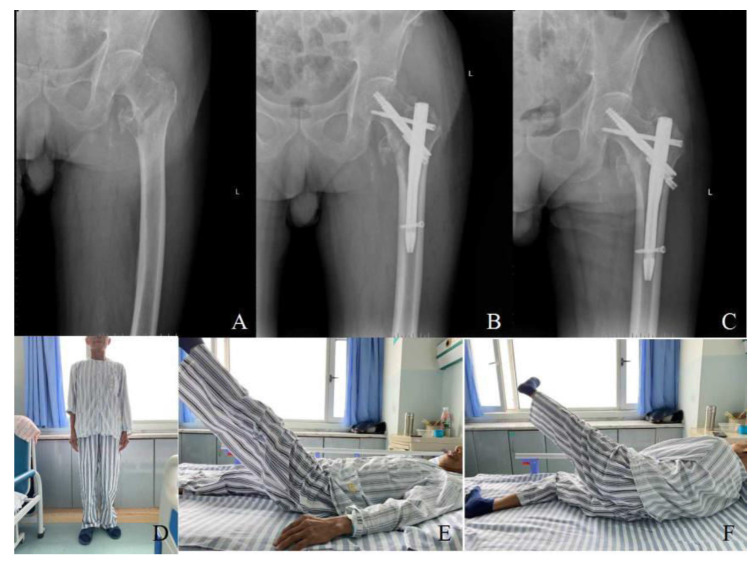

Methods: Eighty-two elderly patients with intertrochanteric femoral fractures treated at Xiangyang No. 1 People's Hospital affiliated with Hubei University of Medicine from December 2021 to 2022 were retrospectively analyzed. They were categorized into three surgical groups: PFBN (22 cases), Inter-TAN (20 cases), and PFNA (40 cases). Preoperative demographics and fracture characteristics were compared, alongside intraoperative and postoperative metrics like operative time and complication rates.

Results: In the PFBN group, operative time, fluoroscopy use, blood loss, and transfusion were higher, but postoperative weight-bearing, healing, and hospital stay were shorter compared to the Inter-TAN and PFNA groups (P<0.05). Inter-TAN had a significantly shorter postoperative weight-bearing time than PFNA (P<0.001). Other compared factors showed no significant differences between groups (P>0.05), including complication rates and scores at 6-month follow-up.

Conclusions: PFBN, a novel surgical approach for intertrochanteric fractures in elderly patients, outperforms Inter-TAN and PFNA by accelerating early weight-bearing and hastening fracture recovery.